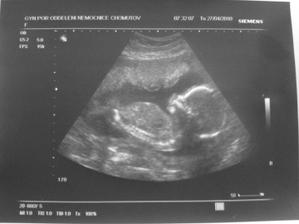

- 27.4.2010 velký UTZ v nemocnici - ten máme za sebou, avšak pořád nevíme co to bude, páč naše malá prdelka měla mezi nožkama pupečníkovou šňůru

- 5.5.2010 jdeme na srdíčko a pak šup k Dr. G - tak vše je ok, a hlavně s největší pravděpodobností to bude malá slečna 🙂, váhový přírůstek 2 kg